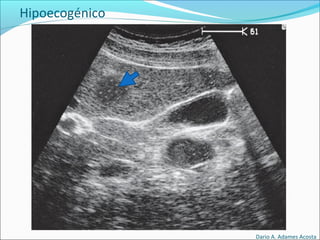

Hipoecogénico

El elemento objetivado es de color menos intenso (mas

oscuro) que los elementos circundantes.

Hipoecogénico

Dario A. Adames Acosta